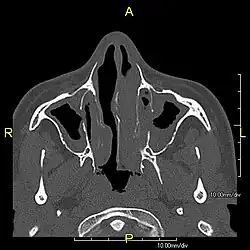

| Complications | Chronic recurrent respiratory infections, including sinusitis, bronchitis, pneumonia, and otitis media.[2] |

Around 80% of people with primary ciliary dyskinesia experience respiratory problems beginning within a day of birth. Many have a collapsed lobe of the lung and blood oxygen low enough to require treatment with supplemental oxygen.[1] Within the first few months of life, most develop a chronic mucus-producing cough and runny nose.[1] The main consequence of impaired ciliary function is reduced or absent mucus clearance from the lungs, and susceptibility to chronic recurrent respiratory infections, including sinusitis, bronchitis, pneumonia, and otitis media. Progressive damage to the respiratory system is common, including progressive bronchiectasis beginning in early childhood, and sinus disease (sometimes becoming severe in adults). However, diagnosis is often missed early in life despite the characteristic signs and symptoms.[2] In males, immotility of sperm can lead to infertility, although conception remains possible through the use of in vitro fertilization, there also are reported cases where sperm were able to move.[8] Trials have also shown that there is a marked reduction in fertility in females with Kartagener's syndrome due to dysfunction of the oviductal cilia.[9]

Many affected individuals experience hearing loss and show symptoms of otitis media which demonstrates variable responsiveness to the insertion of myringotomy tubes or grommets. Some patients have a poor sense of smell, which is believed to accompany high mucus production in the sinuses (although others report normal – or even acute – sensitivity to smell and taste). Clinical progression of the disease is variable, with lung transplantation required in severe cases. Susceptibility to infections can be drastically reduced by an early diagnosis. Treatment with various chest physiotherapy techniques has been observed to reduce the incidence of lung infection and to slow the progression of bronchiectasis dramatically. Aggressive treatment of sinus disease beginning at an early age is believed to slow long-term sinus damage (although this has not yet been adequately documented). Aggressive measures to enhance clearance of mucus, prevent respiratory infections, and treat bacterial superinfections have been observed to slow lung-disease progression. The predicted incidence is 1 in approximately 7500.[10]